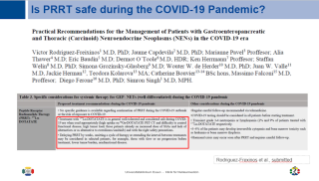

Continuation of care for oncology patients during pandemic

Prof. Ken Herrmann covers the organizational considerations, logistical challenges and medical implications to ensure continuation of care for oncology patients during pandemic